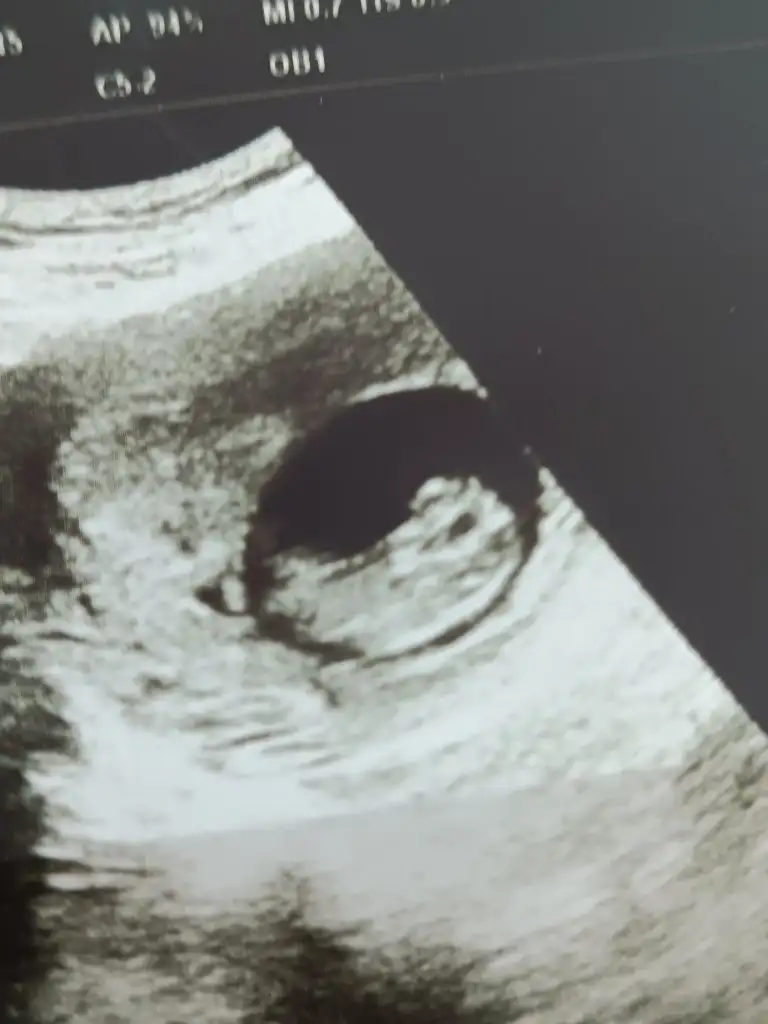

Herkese merhaba, bugün (11+4) ikili test muayenesine girdim. Sonuç için haftaya randevu verdi ama kan testi sonuçlarını kontrol ederken grafik raporun da çıktığını gördüm (çalışıldı yazıyor tabii sadece, gitmeden göremem grafiği). Ense kalınlığı 1.1 mm, burun kemiği oluşmuş dendi muayenede, papp-a 3,19 bhchg 84,55 çıkmış. Bu şekilde bir anlam ifade etmediğini biliyorum ama bir fikri olan çıkar belki diye sormak istedim🤭Fetal dna randevum da haftaya.

Kızımdan farklı duruyor onun da ultrasonuna bakıyorum 😊 günumuzden gerideydik,yetişmişiz çok şükür. Tesekkr ederim fikrini belirttiğin için 🌼

Merhabalar,11+5teyiz su an,ikili tarama testi yaptırdık,sonucu bugun öğrendik. Şükür testte bebekle alakali bir problem yok ama papp-a MoM degeri 0.5in altinda geldi,bu gibi durumlarda annede kanda pıhtılaşma olma ihtimali cok yuksekmis,gerekli testleri yaptirmak icin yonlendirildik. Daha once boyle bir sey duyaniniz var mi?